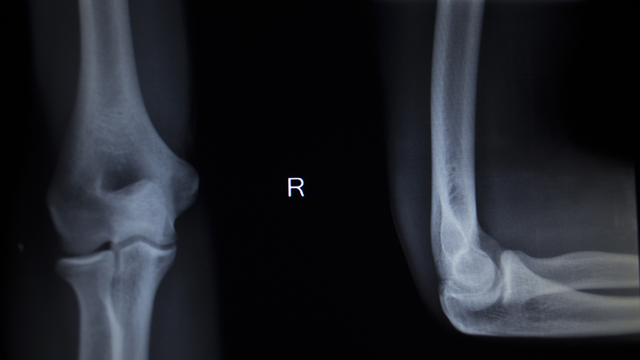

Chẩn đoán bệnh